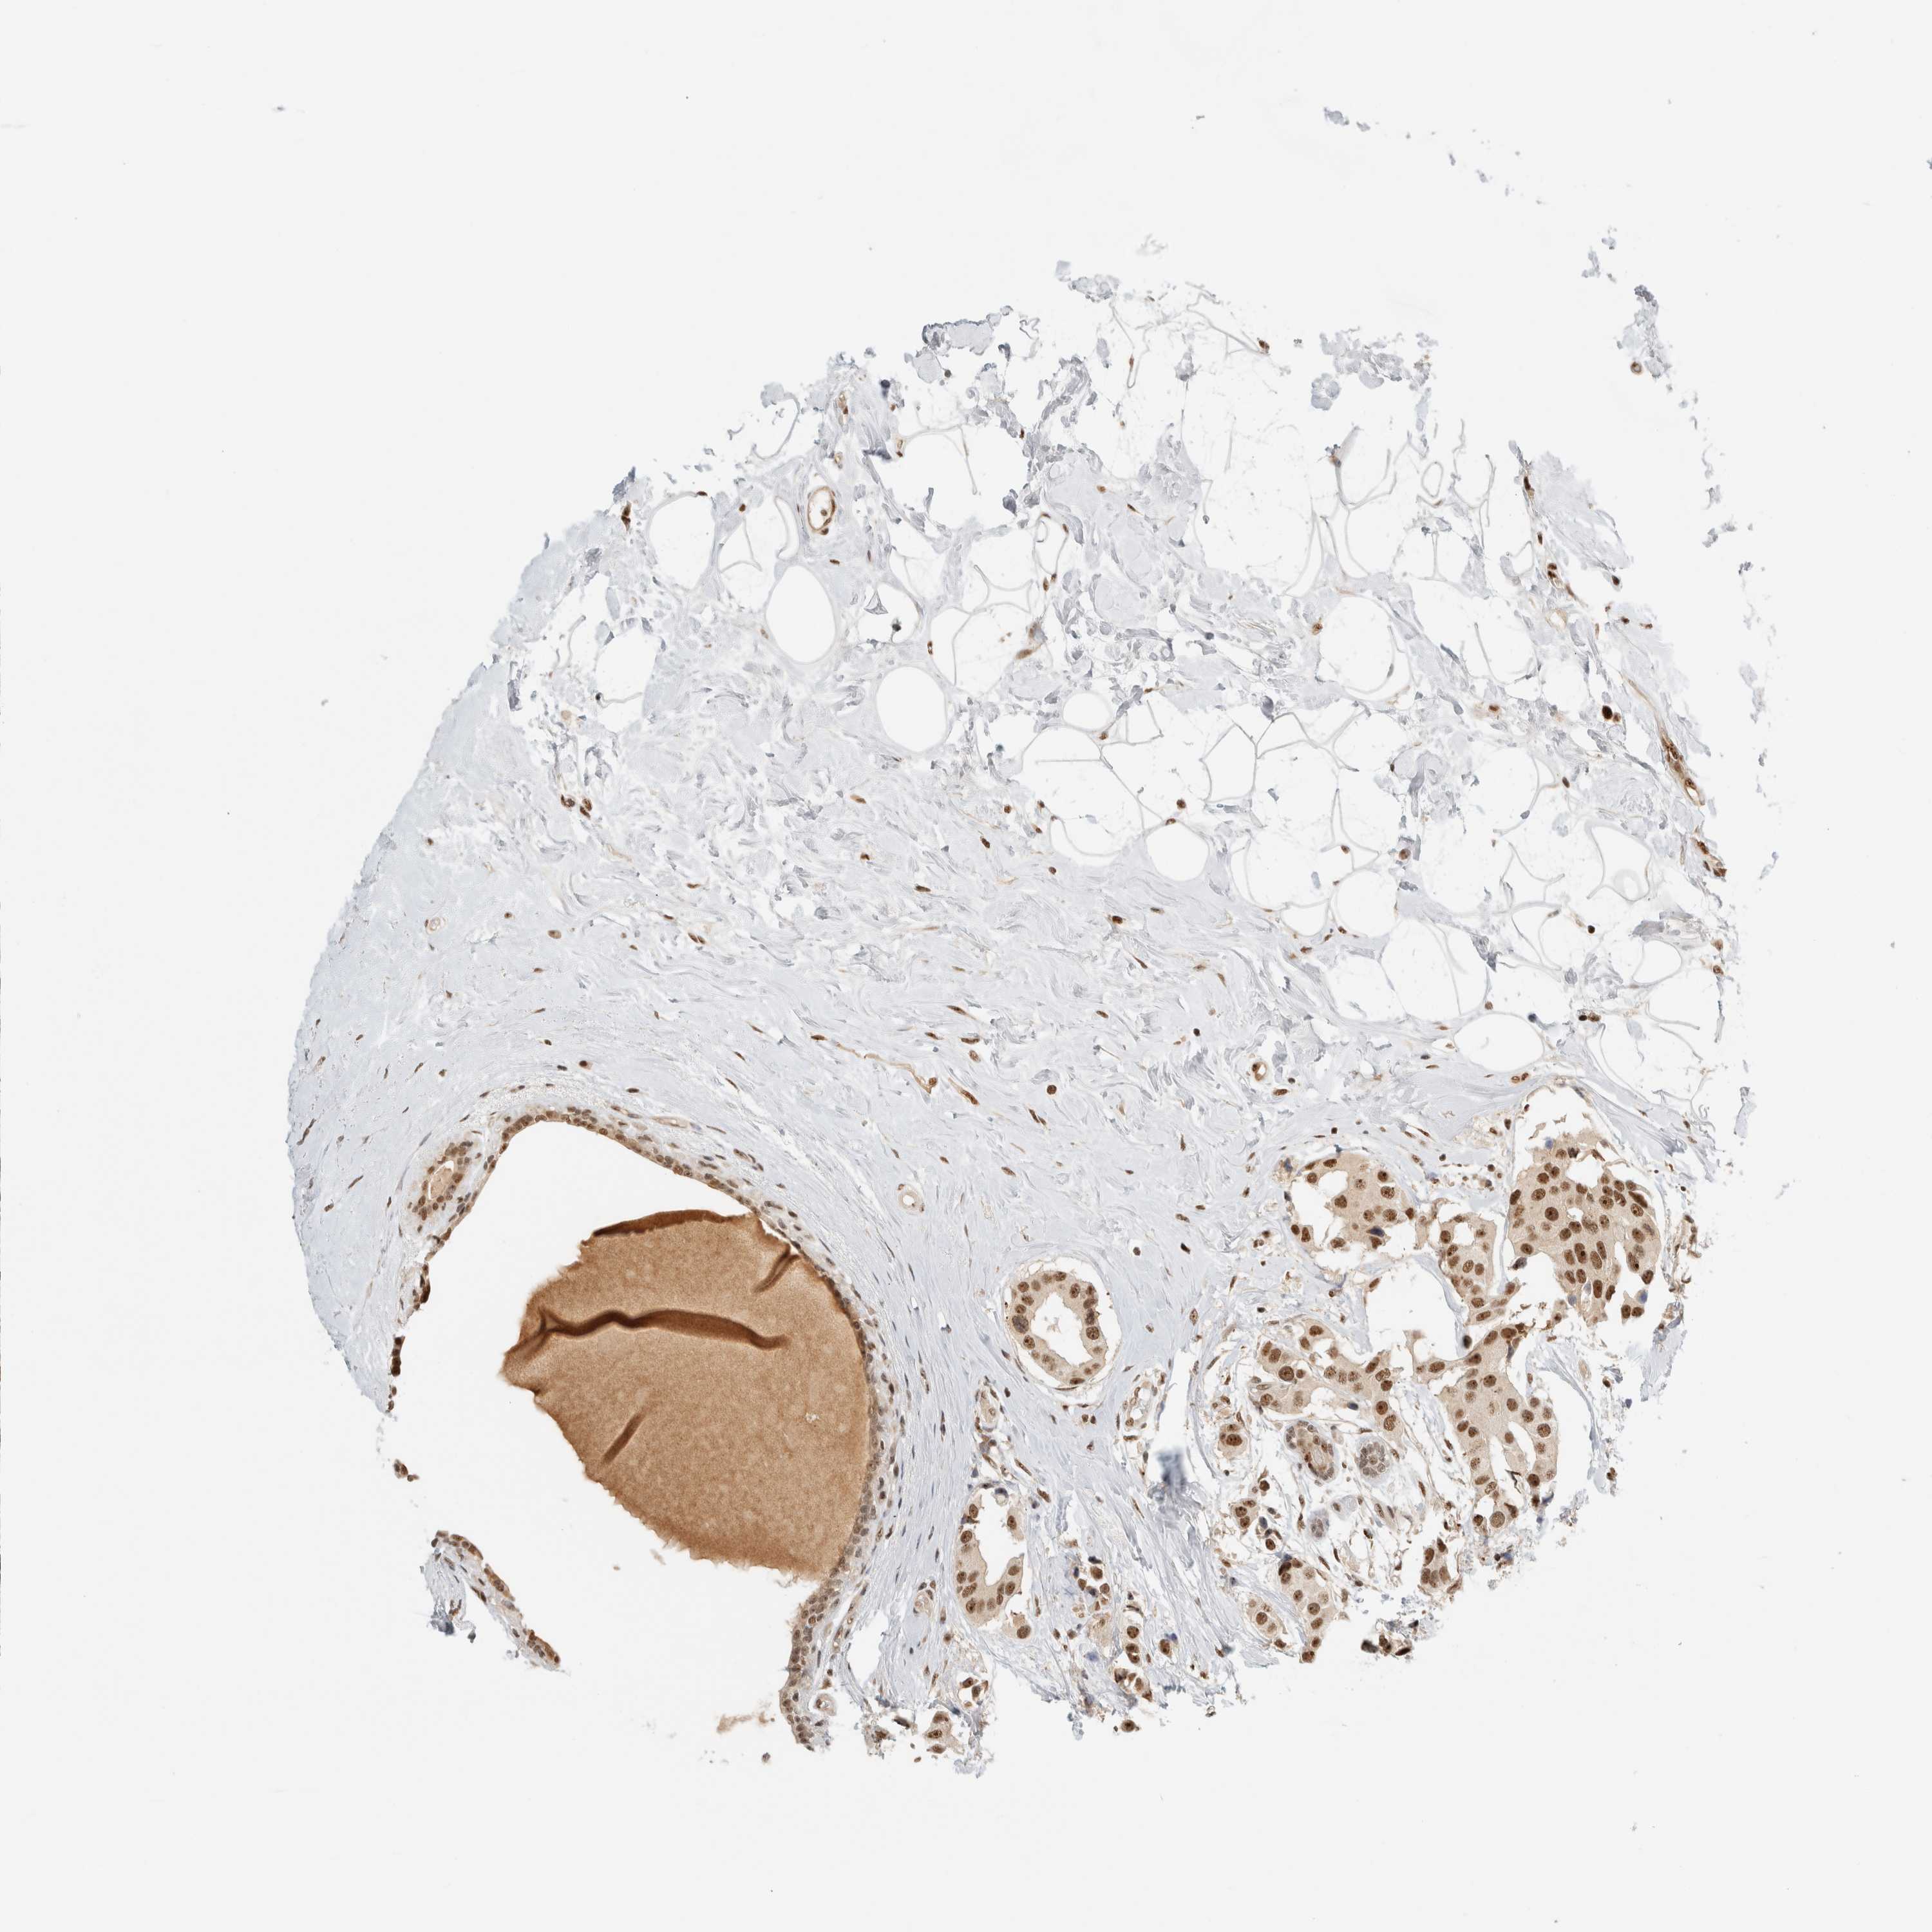

EBNA1BP2

• EBNA1BP2

CANCER BREAST CANCER Show tissue menu

BRCA TCGA BRCA VALIDATION PROTEIN EXPRESSION

Breast cancer

Human cancer

Breast invasive carcinoma

EBNA1BP2 is not prognostic in Breast Invasive Carcinoma (TCGA)